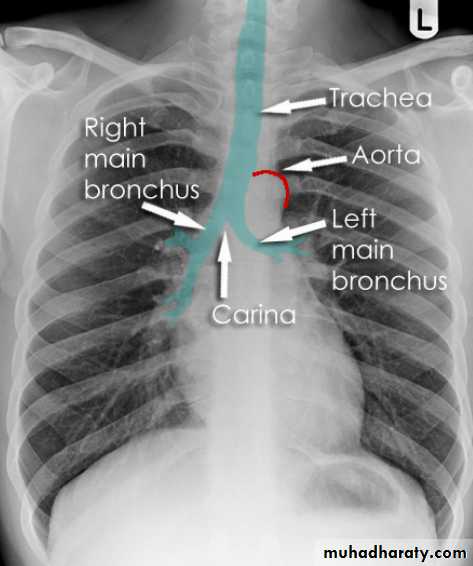

Hilar structuresThe hila (lung roots) are complicated structures mainly consisting of the major bronchi and the pulmonary veins and arteries. These structures pass through the narrow hila on each side and then branch as they widen out into the lungs. The hila are not symmetrical but contain the same basic structures on each side.

Key points

Each hilum contains major bronchi and pulmonary vessels

There are also lymph nodes on each side(not visible unless abnormal)

The left hilum is often higher than the right

Both hila should be of similar size and density. If either hilum is bigger and more dense, this is a good indication that there is an abnormality.